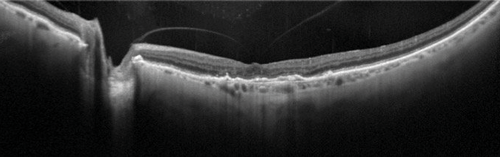

Figure 3: Widefield, high resolution OCT of vitreomacular adhesion (OS).

On Heidelberg Spectralis, 55 degrees widefield, ART of 100.

Apart from OCT imaging having an obvious role in diagnosis of medical retinal conditions such as age-related macular degeneration (AMD), it has allowed diagnosis of various vitreoretinal conditions such as macular holes and epiretinal membranes [12]. OCT imaging can complement vitreoretinal surgery by imaging the vitreomacular interface and may be becoming increasingly useful in clinical practice. For example Steel D et al. [13] determined that the likely success of macular hole closure using ocriplasmin can be predicted from OCT measurements taken during treatment. Higher resolution wide-field OCT imaging has become possible with the use of the Topcon swept source systems and Heidelberg systems, in which details of the posterior vitreous, macular and optic disc can be seen in one image (Figure 3). Vitreoretinal surgery maybe further helped with intraoperative OCT, for example with the use of Zeiss and Optovue systems [12].